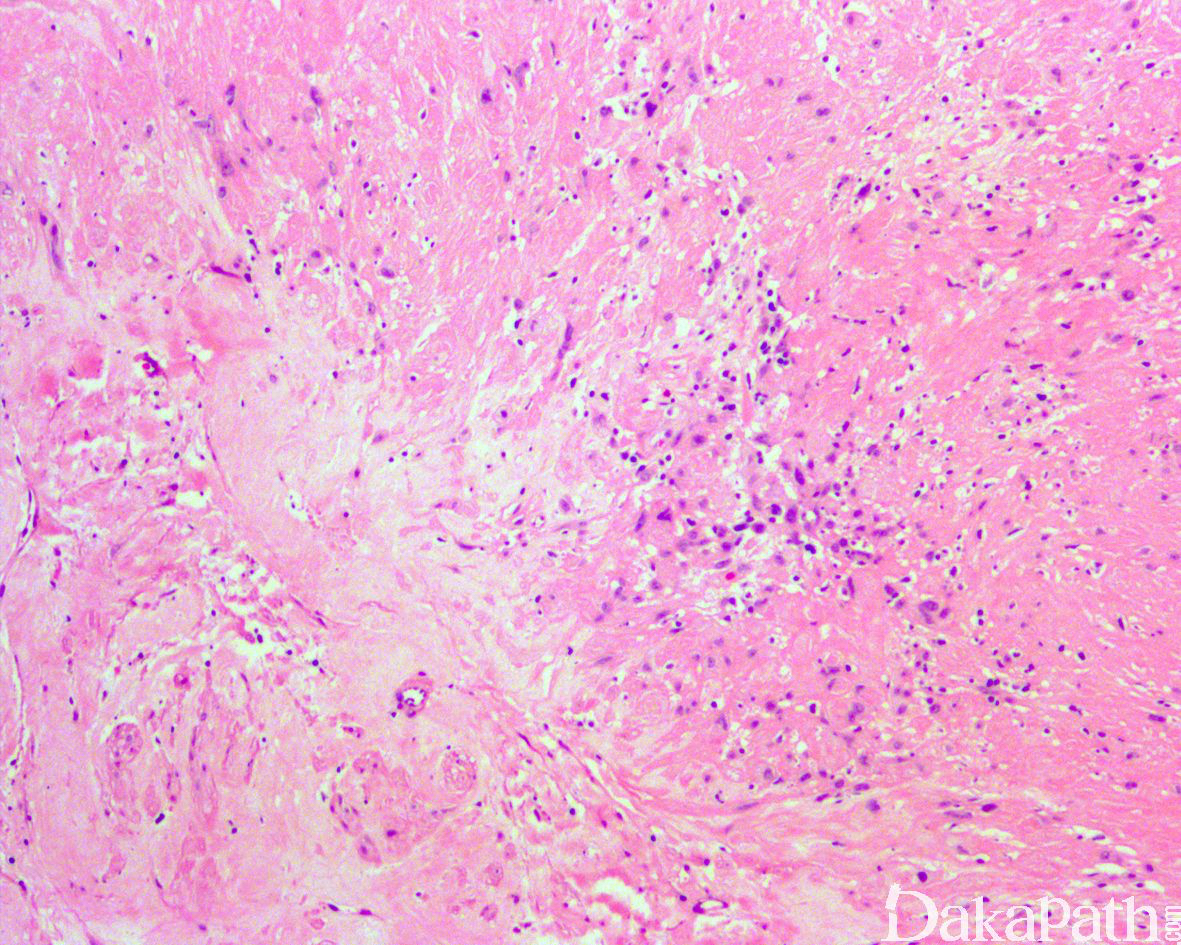

在经典型神经鞘瘤形态基础上伴有退变性细胞核多形性或广泛的玻璃样变,无瘤细胞密度明显增多,无核分裂象,无肿瘤性坏死。

表达 S100 蛋白和 SOX10,Ki67 增殖指数低

神经鞘瘤恶性转化:罕见,瘤细胞密度增高,异型性明显,核分裂象活跃,伴有坏死,Ki67 增殖指数表达增高,S100 蛋白表达减少;H3K27ME3 表达缺失。